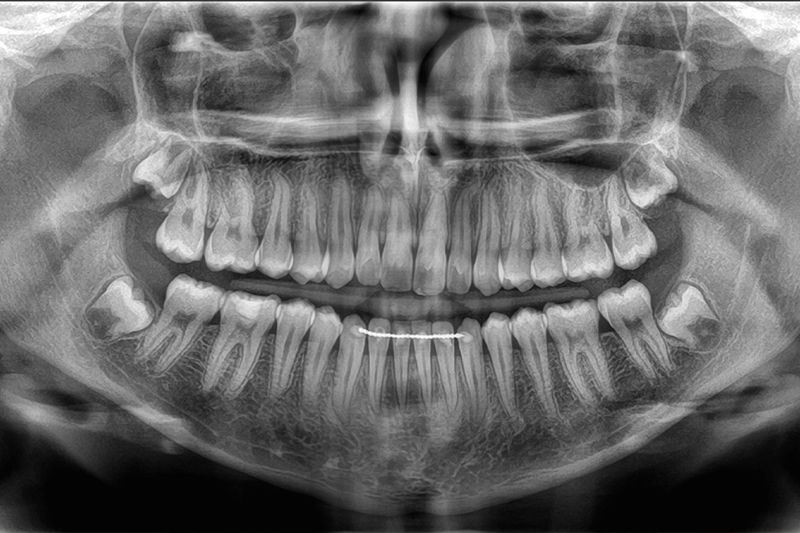

Pano in Pembroke Pines

Pano